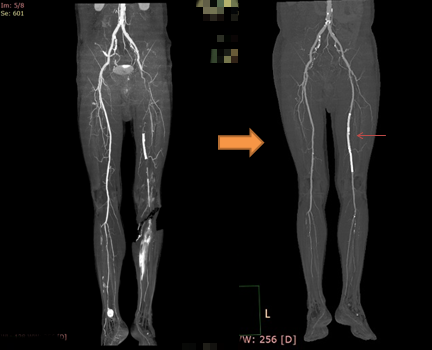

“直接恢复”是利用外科或腔内治疗的方法恢复主干动脉的供血,可以理解为“高速公路”拥堵路段的直接疏通。根据病变的不同,医生可以利用“取栓”、“内膜剥脱”等外科办法,或利用“球囊扩张”、“支架置入”、“斑块减容”等腔内手段对堵塞的动脉血管进行直接疏通,以恢复“血管高速公路”的通畅血流。(图一、图二)

▲ 图一 直接恢复之球囊扩张

▲ 图二 直接恢复之支架植入